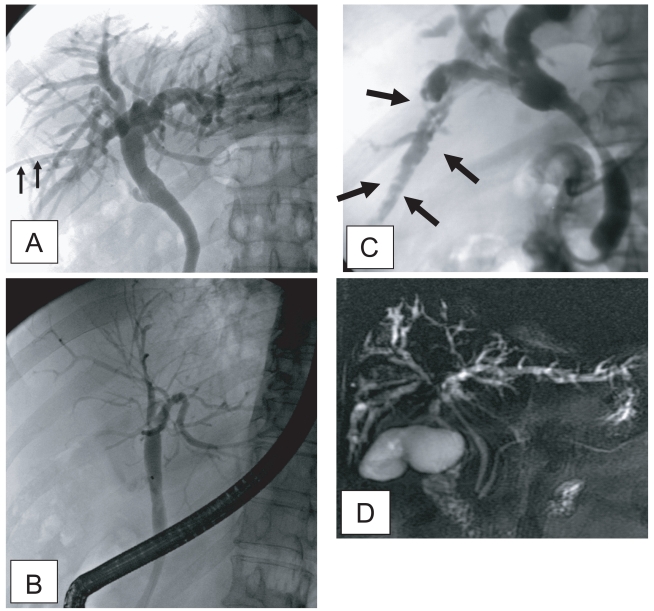

Sonographic findings of diffuse dilatation of the intrahepatic bile ducts and increased periductal echogenicity are known to well reflect pathological changes associated with clonorchiasis (Fig. 2) (Lim et al., 1989; Hong et al., 1994). Sonography is considered a good tool for the diagnosis of clonorchiasis, particularly in cases with a moderate or heavy burden of worms. According to a prior study in Korea, sonography showed low sensitivity and low specificity in the diagnosis of active clonorchiasis (Hong et al., 1998). The study suggested that the low sensitivity was due to a light worm burden and that the low specificity was due to residual pathology after cure.

In a recent study conducted by us in China, increased periductal echogenicity and floating echogenic foci in the gallbladder were proposed as the 2 most significant sonographic findings of active clonorchiasis (Choi et al., 2004). Increased periductal echogenicity represents a thickening of the ductal wall according to mucosal hyperplasia and periductal fibrosis, and the floating echogenic foci indicate worms or desquamated material in the gallbladder (Figs. 2A, B, C) (Lim et al., 1989; Hong et al., 1994; Choi et al., 1999). In our study in China, increased periductal echogenicity showed a sensitivity and specificity for active clonorchiasis of 35% and 91%, respectively (Choi et al., 2004). Floating echogenic foci in the gallbladder had a sensitivity and specificity of 28% and 94%, respectively. However, floating echogenic foci within the gallbladder have been rarely documented in Korea (Lim et al., 1989; Lim, 1990).

In the past literature, diffuse dilatation of the intrahepatic bile ducts on sonographic examination has been considered a hallmark of clonorchiasis (Lim et al., 1989; Lim, 1990; Hong et al., 1994). Diffuse dilatation of the intrahepatic bile ducts was found in an about half (49-52%) of the control subjects in either present endemic area or past endemic area (Fig. 2D) (Hong et al., 1998; Choi et al., 2004). Thus, patients only with a dilatation of the intrahepatic bile ducts detected by sonography cannot be considered candidates for praziquantel treatment (Chen et al., 1994; Hong et al., 1998; Choi et al., 1999). In an experimental study, the histopathological specimens at 18 mo after treatment with praziquantel showed that periductal inflammation has almost resolved but moderate dilatation of the intrahepatic ducts and mucosal hyperplasia persisted (Choi et al., 1999). The periductal fibrosis minimally resolved.

Fig. 2

Liver sonograms of clonorchiasis. A. In a 57-year-old man, transverse scan of the left hepatic lobe, showing mild dilatation of the intrahepatic bile ducts (arrows). B. In a 56-year-old man with the increased periductal echogenicity (arrows) along the dilated intrahepatic bile ducts. C. Oblique scan of the gallbladder of a heavily - infected Chinese man with several floating echogenic foci (arrows), which probably indicate worms or desquamated materials. D. Mild dilatation of the intrahepatic bile ducts in the central liver of a cured 60-year-old man.

Fig. 2 Liver sonograms of clonorchiasis. A. In a 57-year-old man, transverse scan of the left hepatic lobe, showing mild dilatation of the intrahepatic bile ducts (arrows). B. In a 56-year-old man with the increased periductal echogenicity (arrows) along the dilated intrahepatic bile ducts. C. Oblique scan of the gallbladder of a heavily - infected Chinese man with several floating echogenic foci (arrows), which probably indicate worms or desquamated materials. D. Mild dilatation of the intrahepatic bile ducts in the central liver of a cured 60-year-old man.